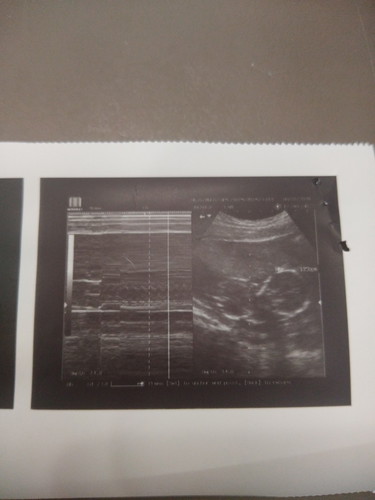

8 months pregnant

Okay lang po ba na wala akong karecord record sa baby ko dahil po sa ECQ at last time po kasagsagan ng pag aalburoto ng bulkang taal kaya hnd makapagpacheck up. Kinakabahan po kasi ako lalo at first time mom ako. Pero complete naman po ako sa vitamins dahil nung 4 months tyan ko nakapagpacheck up ako pero after that hnd na ako nakapag follow up. Pano po masasabi na ayos lang si baby ? Thank you po